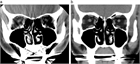

1. 鼻閉感は鼻閉塞に起因することが多いが、上咽頭疾患など鼻腔外の要因でも来し、さらに心身症や萎縮性鼻炎など、閉塞性の病変がなくても生じ得る。

1. 原疾患の病態(感染やアレルギーなど)に応じた治療を行う。鼻粘膜腫脹に対する対症療法としては、鼻処置などによる血管拡張と粘膜下浮腫の除去を行う。